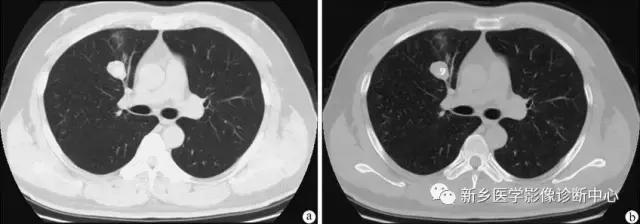

肺内血肿

有外伤史,胸痛,痰中带血或咯血。早期多为大片实变影,边缘模糊,2周后可出现类圆形密度均匀,边界清楚的球形肿块影。

下图为:车祸2小时血肿,治疗1周血肿,及治疗2周后血肿